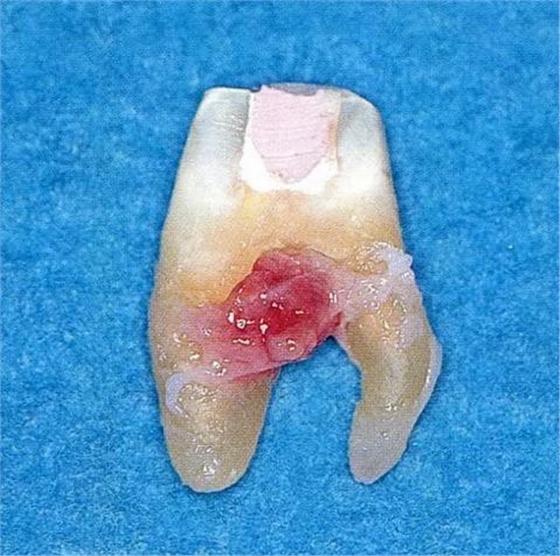

▼圖6-1下頜第一后磨牙的頰舌間存在III度的根分叉病變,預(yù)在進行牙根分割后保留遠中根。

▼圖6-2中下頜第一后磨牙雖然切除了一半,但是遠中根也有2根分根,所以不得已拔除(被拔除遠中根的近中面觀察)。